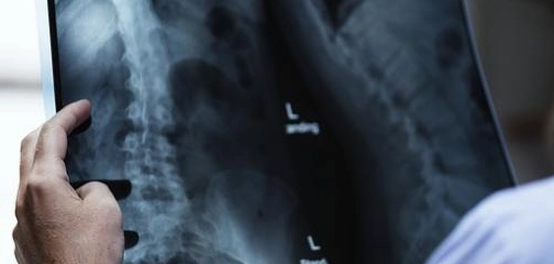

تعتمد الأشعة السينية على توجيه أشعة كهرومغناطيسية عالية الطاقة نحو الجسم، حيث يتم امتصاصها بدرجات مختلفة حسب كثافة الأنسجة. العظام، على سبيل المثال، تمتص كمية أكبر من الأشعة مقارنة بالأنسجة الرخوة، مما يسمح بإنشاء صور واضحة للهيكل العظمي.

الاستخدامات الطبية للأشعة السينية

تُستخدم الأشعة السينية في العديد من المجالات الطبية لتشخيص ومراقبة الحالات الصحية. من بين الاستخدامات الشائعة:

- تشخيص الكسور: تُعتبر الأشعة السينية الأداة الرئيسية للكشف عن كسور العظام وتحديد موقعها وشدتها.